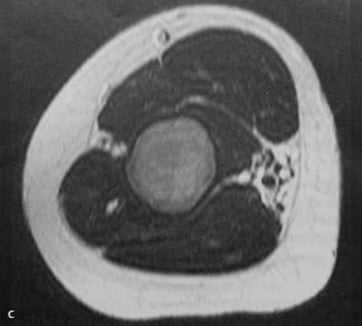

a-d Фиброзная дисплазия. Женщина 48 лет с фиброзной дисплазией, поражающей дистальный отдел плечевой кости: a) На рентгенограмме диафиза плечевой кости определяется кистозное географическое поражение с пузырным расширением. Типичное изображение в виде «битого стекла»;

c) Т2-взвешенная последовательность. Гипоинтенсивный сигнал по отношению к нормальной жировой ткани костного мозга;

d) Т1-взвешенная последовательность после введения гадолиния. Гомогенное на¬копление контрастного вещества в области поражения.